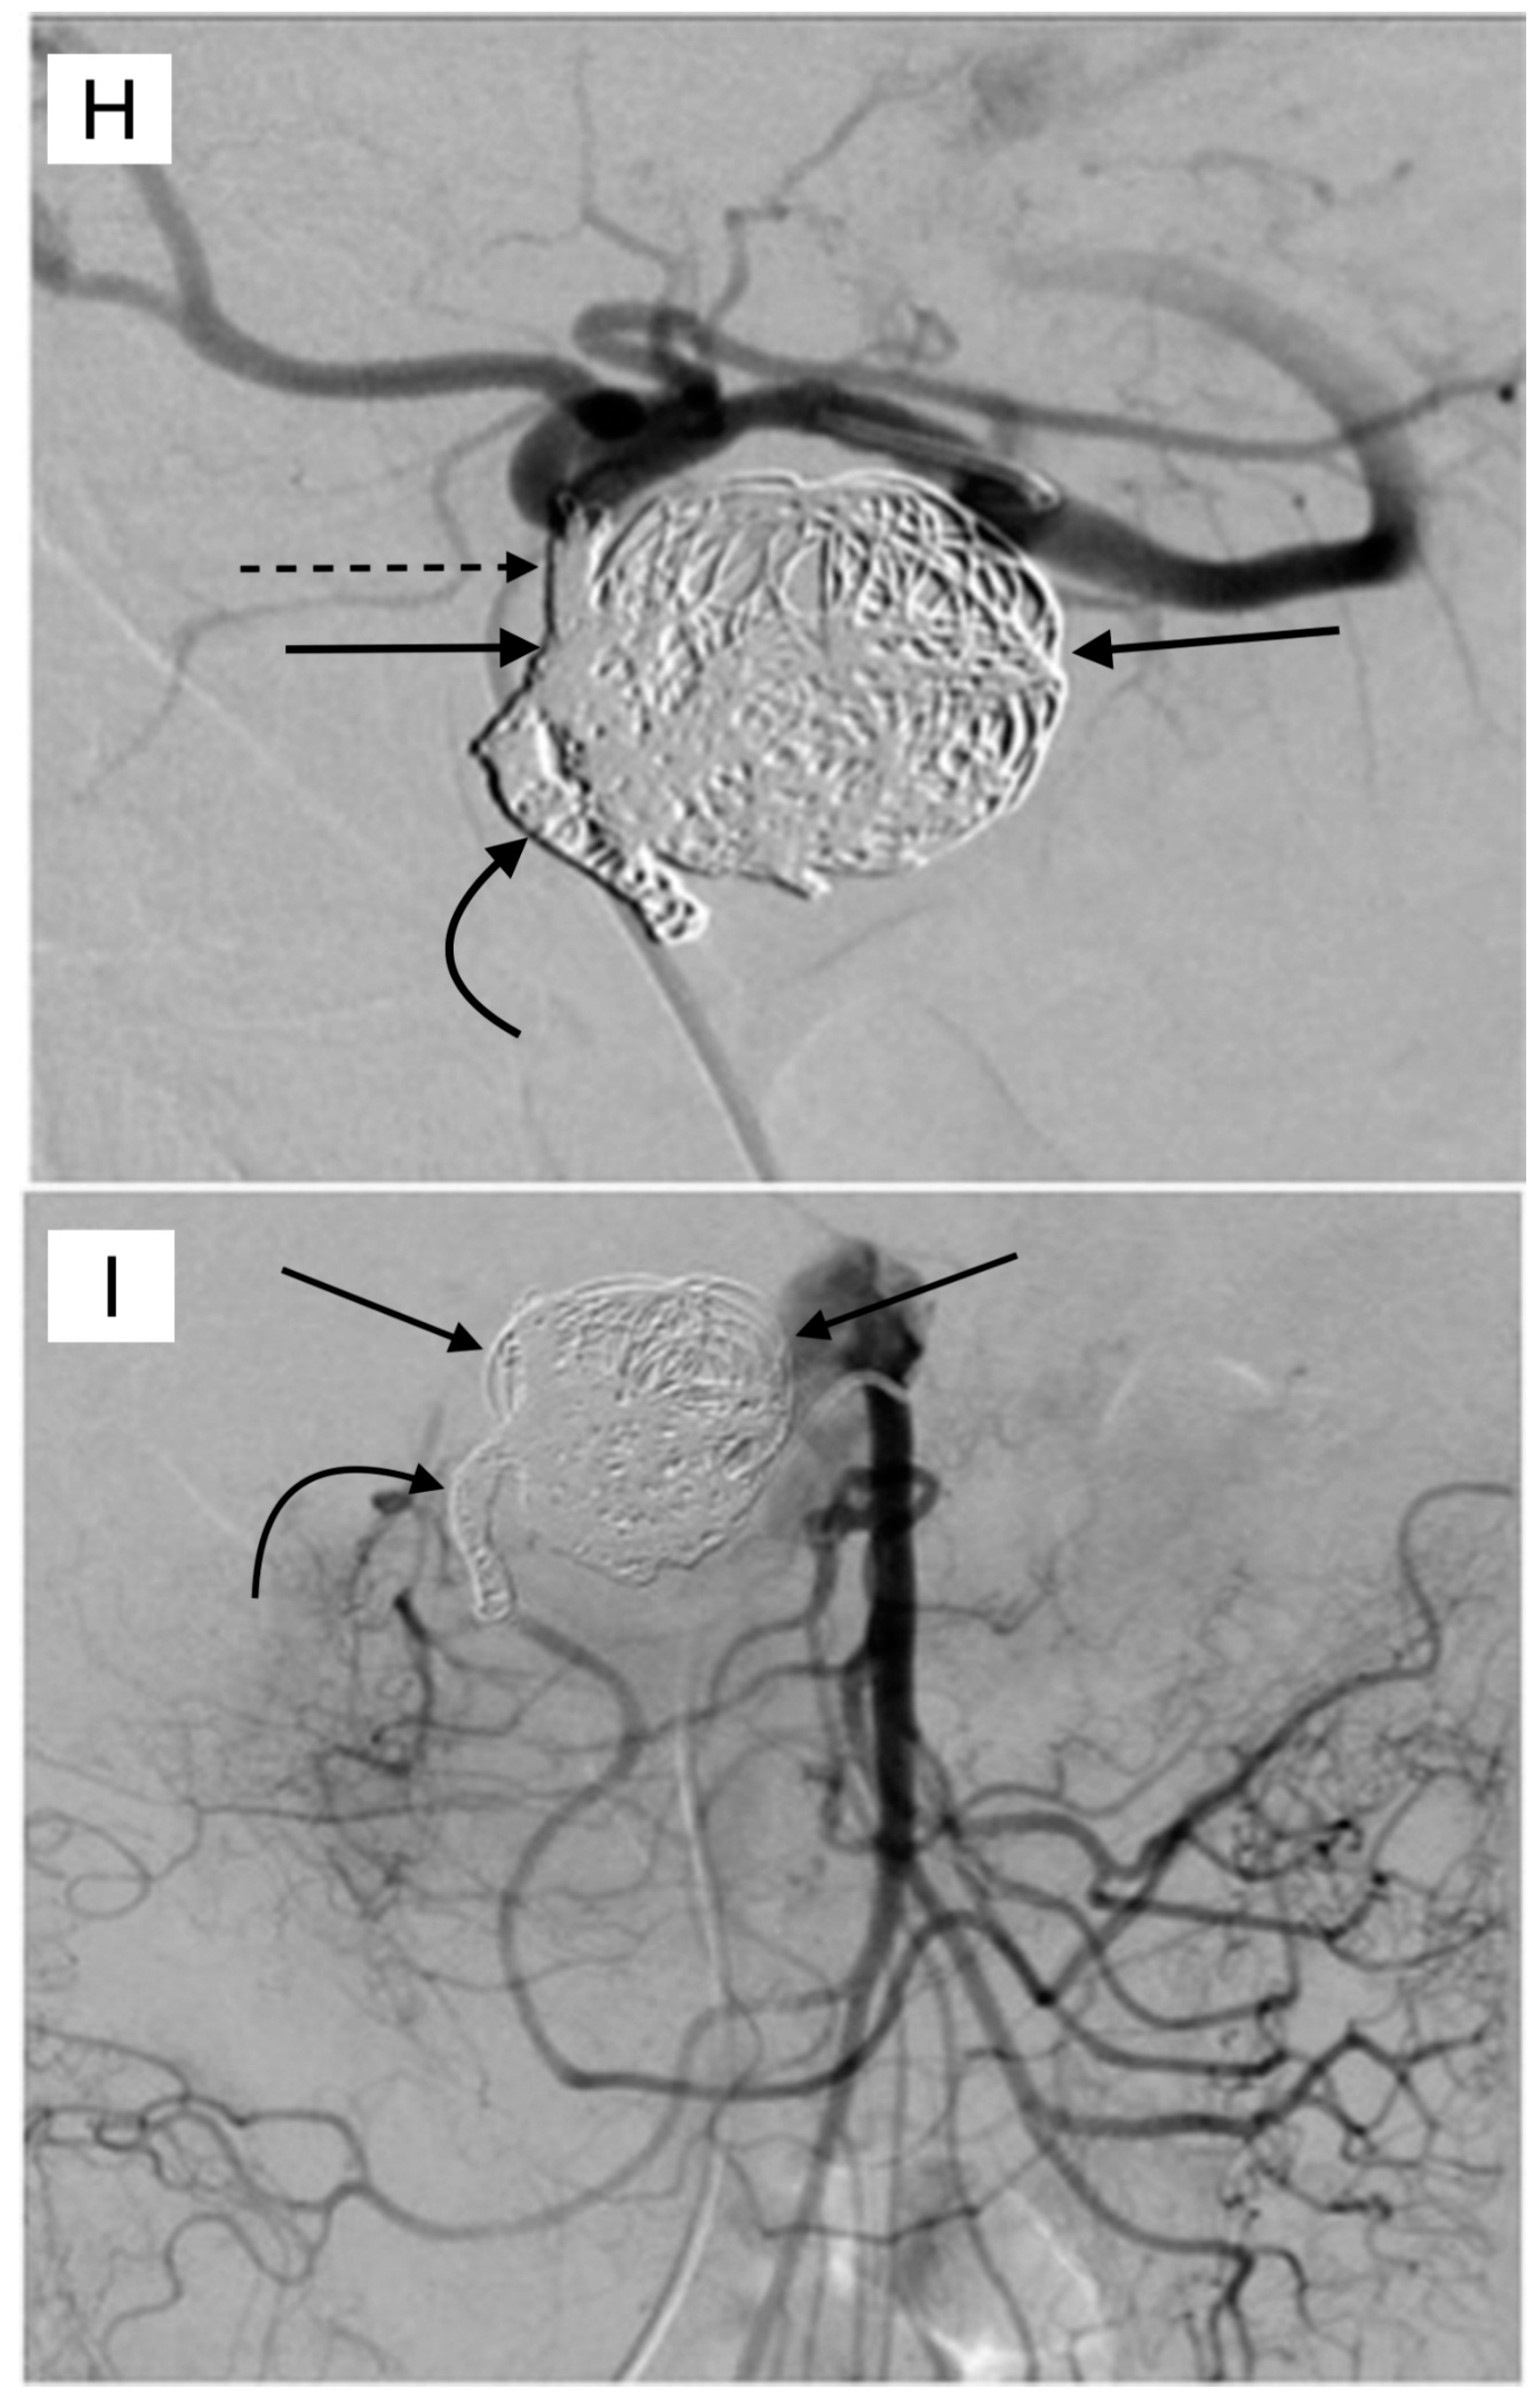

5. Pre-Y-90 GDA Embolization